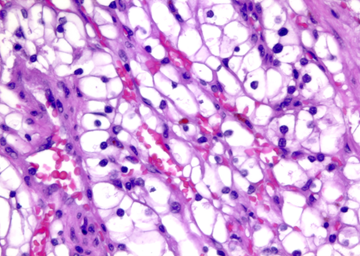

Ung thư biểu mô tế bào thận tế bào kỵ sắc (3-5%)

Đại thể

Khối u thường có kích thước lớn, với kích thước trung vị khoảng 8 cm và dao động từ 1 đến 30 cm, chủ yếu là dạng đặc, chỉ hiếm gặp các trường hợp dạng nang. Khối u có ranh giới rõ nhưng không có bao thực sự. Mặt cắt có màu nâu nhạt đến xám, trong đó mức độ đậm nhạt thay đổi của màu nâu gụ tương quan với số lượng tế bào có bào tương eosin. Các vùng màu trắng ngà, mềm, dạng thịt gợi ý sự chuyển dạng sarcomatoid. Xuất huyết và hoại tử được ghi nhận trong khoảng 25% trường hợp. Xâm lấn tĩnh mạch thận hiếm gặp. Sẹo trung tâm hiện diện trong khoảng 15% các trường hợp.

Vi thể

Mô tả vi thể (mô học) điển hình cho thấy khối u thường gồm các đám đặc tế bào, được chia cắt bởi các vách xơ–mạch máu không hoàn chỉnh, tạo nên kiểu phát triển bè rộng; kiểu sắp xếp dạng ổ hoặc dạng phế nang gặp ít hơn. Các tế bào lớn với bào tương nhạt màu, dạng lưới mịn là đặc trưng nhất và xác định thực thể khối u này, trong đó thuật ngữ chromophobe phản ánh đặc điểm bào tương kém bắt màu. Xen kẽ là các tế bào nhỏ hơn với bào tương eosin. Các tế bào lớn có bào tương rất phong phú, đến mức trong một số mặt cắt, nhân không nằm trong mặt phẳng cắt nên tế bào có vẻ như không nhân, đây là một dấu hiệu gợi ý chẩn đoán mô học mềm. Ranh giới tế bào rõ, tạo hình ảnh giống tế bào thực vật. Có quầng sáng quanh nhân kiểu giả koilocyte. Nhân thường tăng sắc, màng nhân không đều và nhăn nheo, tạo hình ảnh dạng nho khô, kèm hiện tượng hai nhân khá thường gặp.

Hình 10. ChRCC thể điển hình được cấu tạo bởi các tế bào đa giác lớn với bào tương sáng, dạng lưới, xen kẽ với các tế bào nhỏ hơn có bào tương eosin. Lưu ý rằng các tế bào lớn có bào tương rất phong phú đến mức trong một số mặt cắt mô, nhân không nằm trong mặt phẳng cắt, khiến các tế bào này có hình ảnh như không nhân.

Ở kiểu hình eosinophilic, ít nhất 80% khối u phải được cấu tạo bởi các tế bào có bào tương eosin; các tế bào này thường nhỏ hơn so với tế bào chromophobe điển hình. Kiến trúc có thể dạng ổ, dạng phế nang hoặc dạng đám đặc, trong đó cấu trúc dạng ổ gặp thường xuyên hơn ở biến thể eosinophilic so với thể điển hình, còn lại các đặc điểm mô học tương tự thể điển hình.

Hình 11. ChRCC kiểu eosinophilic được đặc trưng bởi thành phần chủ yếu, ít nhất 80%, là các tế bào có bào tương eosin, kèm mức độ không điển hình tế bào học nhẹ, với nhân nhăn nheo và hiện tượng hai nhân phân bố rải rác lan tỏa.